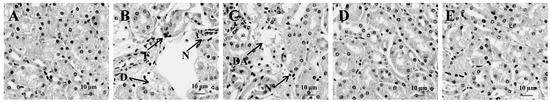

3.4. Histopathological Analysis of Spleen in CYP-Treated Mice